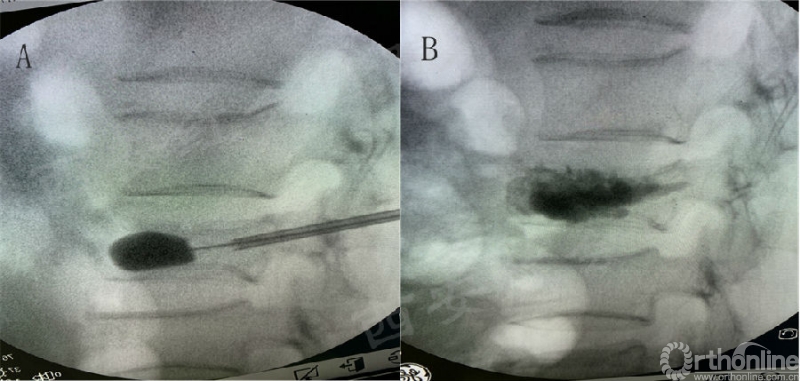

② 为防止球囊撑开造成的骨块向椎管移动,球囊需放置于椎体前1/2至2/3处,在复位的基础上利用球囊在椎体内形成的低压区,降低骨水泥渗漏的风险(图4);

图4 爆裂骨折PKP手术操作步骤

A.球囊放置于椎体前1/2至2/3处;B.骨水泥分布满意,无明显渗漏